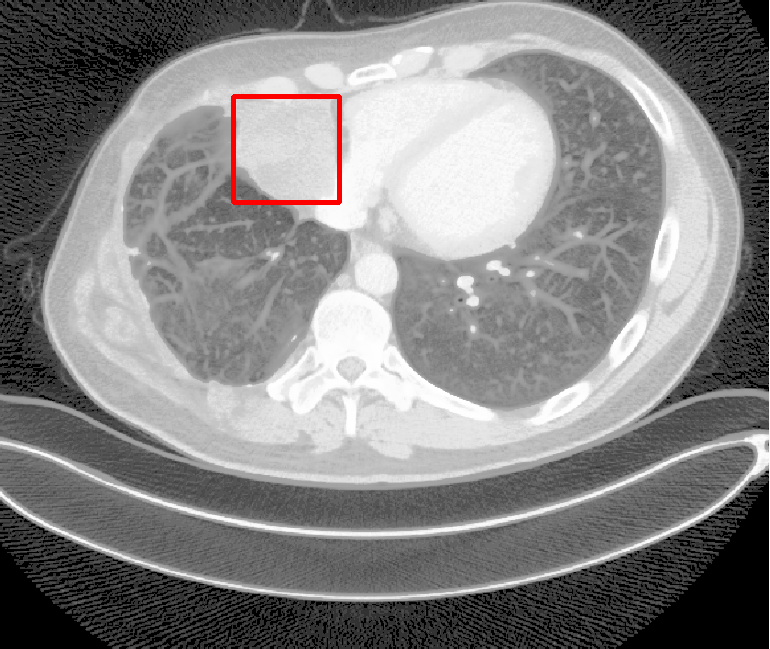

| (a) Ground Truth | (b) Faster R-CNN | (c) FPN | (d) Proposed |

In real-world scenarios, body lesions usually have arbitrary size. For instance, in the DeepLesion [14] dataset, the lesion size ranges from 0.21 mm to 342.5 mm. Since most of the established CNNs are not robust to handle such spatial scale variations, they have unpredictable behavior in the varying cases. As shown in Fig. 1, both Faster R-CNN and FPN fail to detect tiny lesions in the first row, while they produce small false positive lesions around the actual large lesion locations in the second and third rows.